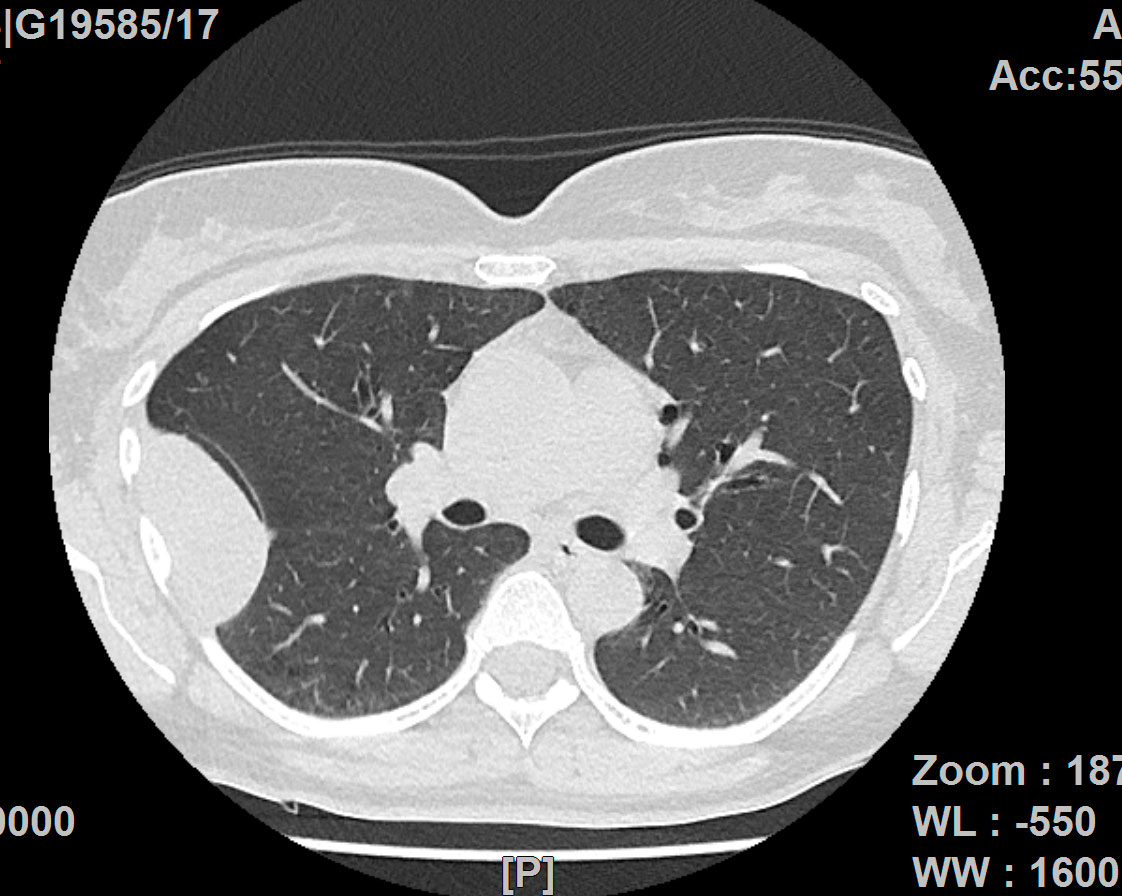

Lungenkrebs

Lungenkrebs befällt etwa 25 Prozent aller Krebskranken und gilt als häufigster Tumor beim Mann. Doch auch immer mehr Frauen sind betroffen. Die chirurgische Therapie ist für uns Mittel der Wahl, sofern keine Fernmetastasen vorhanden sind. Dabei können wir in unserer Klinik technisch hoch anspruchsvolle Lungenoperationen auf endoskopische Weise videoassistiert vorgenommen werden.

Lungenmetastasen

Werden neben Lungenkrebs auch Lungenmetastasen diagnostiziert, stellt das die Medizin vor höchste Herausforderungen. Nur wenige Kliniken sind darauf spezialisiert, bei dieser Erkrankung chirurgisch einzugreifen. Durch besondere fachliche Expertise, einen großen Erfahrungsschatz und die technische Ausstattung ist unsere Klinik Ihr Ansprechpartner, wenn es um die chirurgische Therapie von Lungenmetastasen geht.

Laser-Chirurgie bei Lungenmetastasen

In unserer Klinik für Thoraxchirurgie werden zahlreiche Operationen an der Lunge mit dem modernen 1318NM-Diodenlaser durchgeführt. Das neue Gerät wurde speziell für die Lungenchirurgie entwickelt und hat besondere Eigenschaften, die das Schneiden von Lungengewebe ermöglichen: Mit dem Laser ist der Thoraxchirurg in der Lage, bluttrocken und übersichtlich durch das Lungengewebe zu schneiden. Dadurch können Metastasen und Tumoren, die tief im Lungengewebe liegen, onkologisch sicher entfernt werden. Anhand dieses modernen Verfahrens kann der Thoraxchirurg besonders gewebeschonend vorgehen und zahlreiche Lungenmetastasen entfernen, was mit konventionellen Methoden nicht möglich wäre. So kann die Prognose für den Patienten verbessert werden. Die sogenannte Laser-Metastasektomie ist eine etablierte chirurgische Behandlung, die bundesweit nur in großen Thoraxkliniken vorgenommen wird. Unsere Klinik ist die einzige in Ostwestfalen-Lippe, die Laser-Chirurgie bei Operationen der Lunge anbietet.

- Lungenrundherd (Lungenverschattung)

Chronisch-obstruktive Bronchitis (COPD) und Lungenemphysem

Das Lungenemphysem führt zu einer krankhaften Überblähung der Lunge. Die Behandlung besteht aus Raucherentwöhnung, bronchienerweiternden Medikamenten, Sauerstoffgabe. Im fortgeschrittenen Stadium kann in ausgewählten Fällen durch eine lungenverkleinernde Operation (LVRS) eine Verbesserung der Symptomatik erreicht werden.